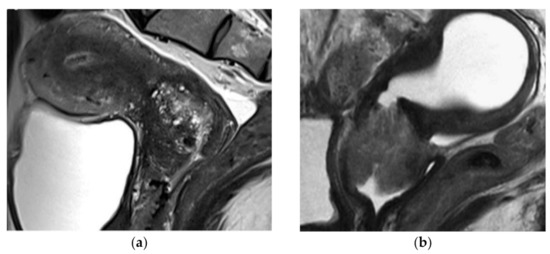

4.1.3. Radiologic Features

- Kido, A.; Mikami, Y.; Koyama, T.; Kataoka, M.; Shitano, F.; Konishi, I.; Togashi, K. Magnetic resonance appearance of gastric-type adenocarcinoma of the uterine cervix in comparison with that of usual-type endocervical adenocarcinoma: A pitfall of newly described unusual subtype of endocervical adenocarcinoma. Int. J. Gynecol. Cancer 2014, 24, 1474–1479. [Google Scholar] [CrossRef]

- Park, K.J.; Kim, M.H.; Kim, J.K.; Cho, K.S. Gastric-Type Adenocarcinoma of the Uterine Cervix: Magnetic Resonance Imaging Features, Clinical Outcomes, and Prognostic Factors. Int. J. Gynecol. Cancer 2018, 28, 1203–1210. [Google Scholar] [CrossRef]